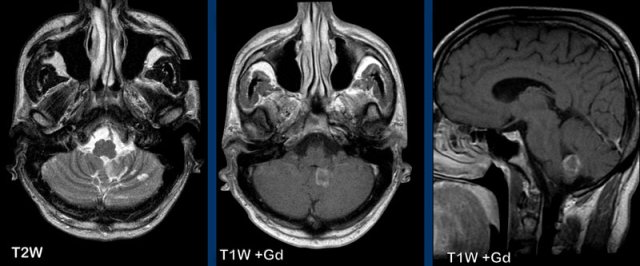

These images are of a 58 year-old male who presented with headache in the sitting and standing position.

Images

A

smooth dural enhancement is present in both the supratentorial and the infratentorial compartment.

Notice the small ventricles.

Continue with the sagittal images...

Image 1

The findings are rather subtle, but there is:

- Sagging of the midbrain with decreased pontomamillary distance, effacement of the suprasellar cistern, flattening of the anterior pons and kinking at the craniocervical junction.

- The hypothalamus is folding over the dorsum of the sella, the pituitary gland is somewhat enlarged (white circle).

- The interthalamic substance is lowered; the posterior part of the corpus callosum is lowered (‘drooping penis sign”). Note the flattening of the supracerebellar cistern.

- In this case the tonsils are in a normal position and there is no herniation (yellow circle).

Conclusion: findings

typical for intracranial hypotension.